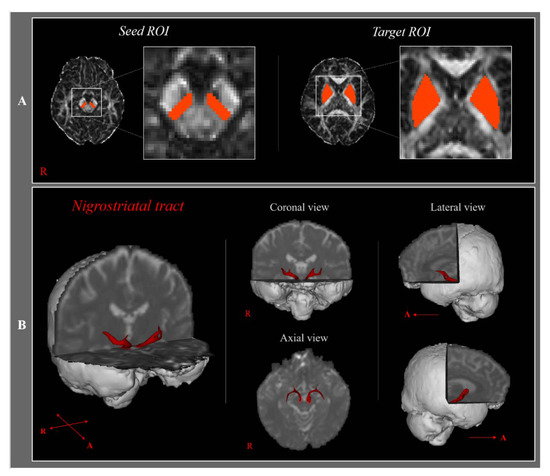

| Nigrostriatal tract | FA | 0.429 (±0.03) | 0.422 (±0.03) | 0.412 (±0.03) | 0.241 |

| TV | 494.354 (±168.24) | 419.647 (±139.31) | 303.611 (±131.43) | 0.001 * | |

| Post-hoc p-value | FA | 0.447 | 0.395 | 0.093 | |

| TV | 0.121 | <0.001 * | 0.026 * |